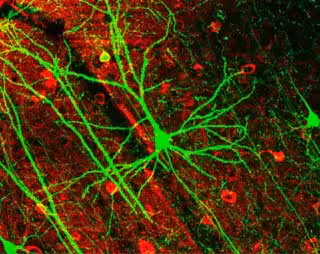

neuronas

NRETS/WIKIMEDIA COMMONS